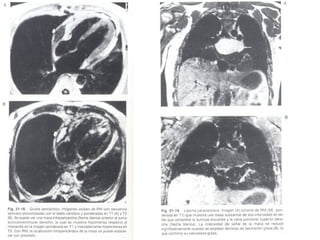

Miocardiopatía hipertrófica enRM. Plano transverso a través de los ventrículos. Hipertrofia del tabique y pared posterolateral de VI. DIASTOLE SISTOLE